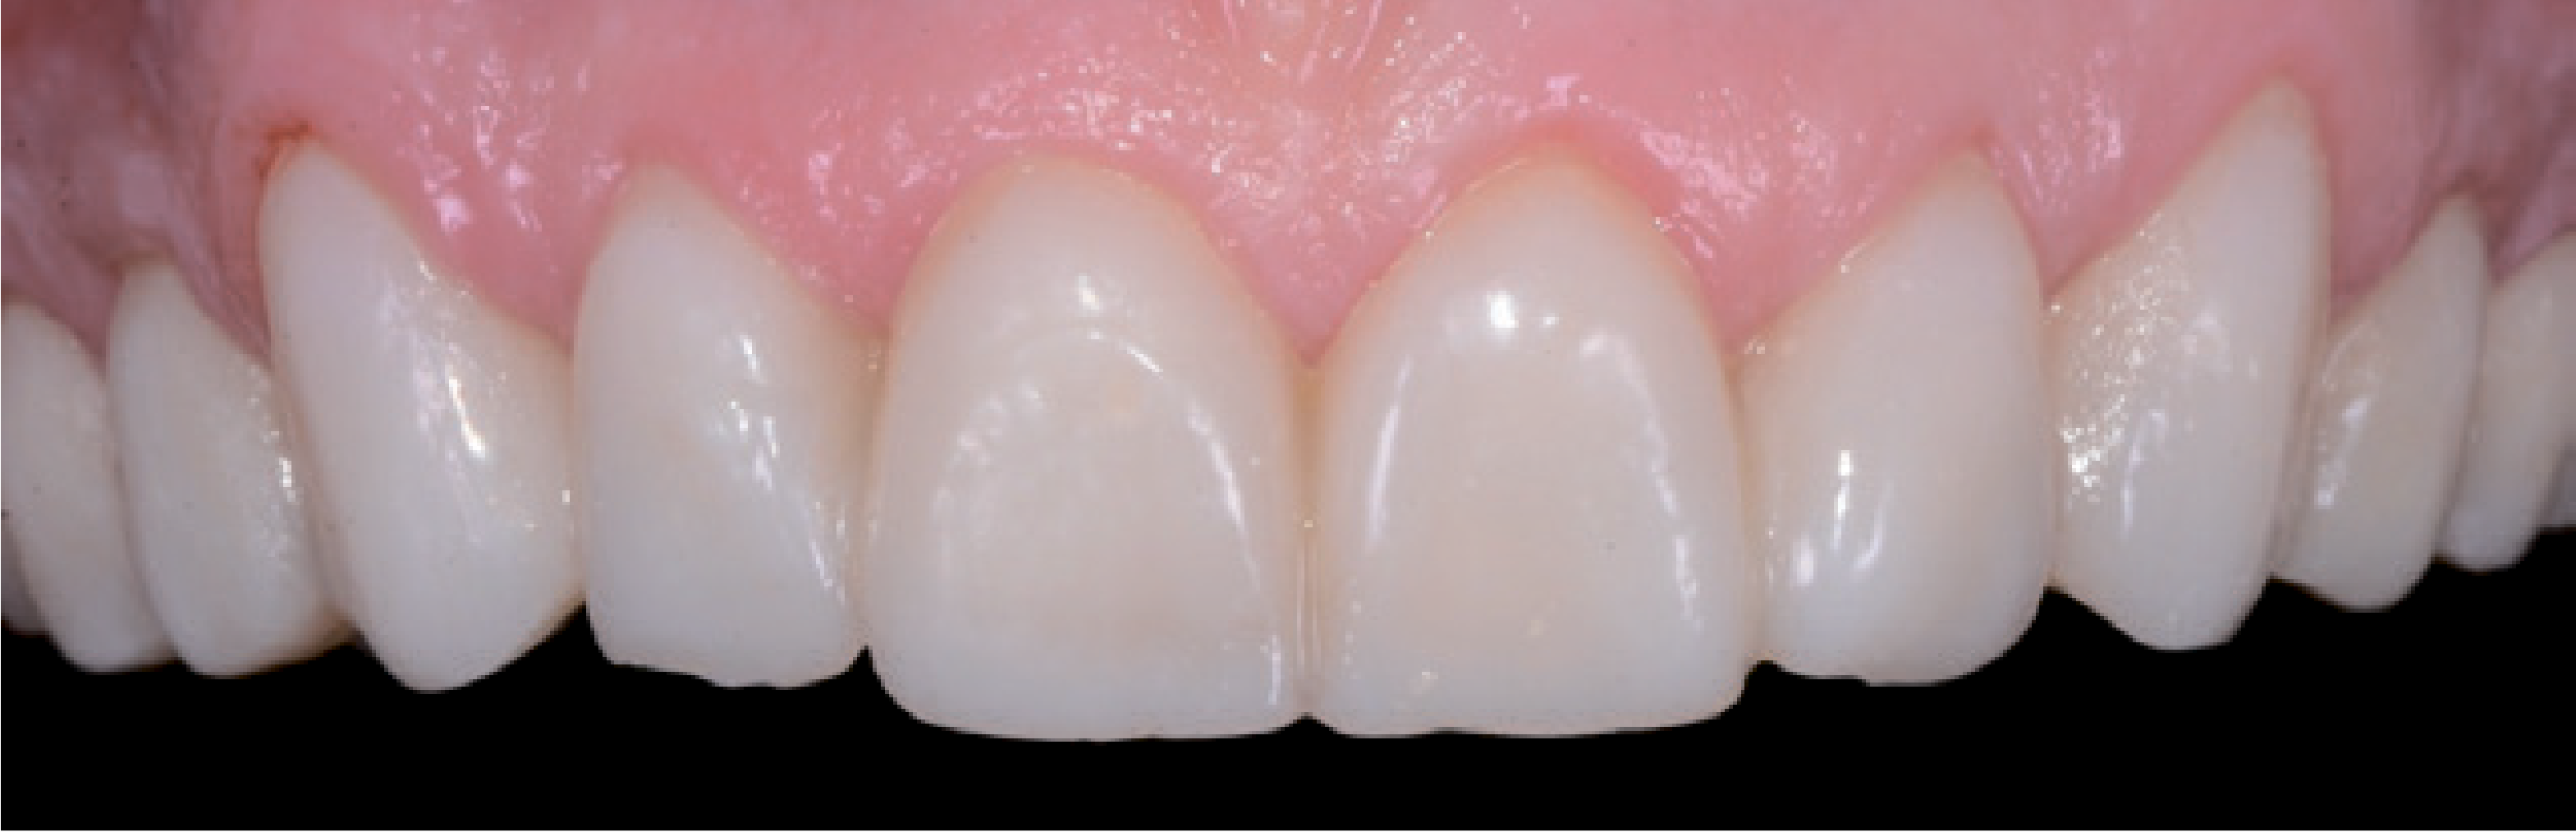

Вініри акуратно встановили вручну. Для цього чинили тиск великим і вказівним пальцями у напрямку від різцевої до пришийкової зони. Коли реставраційні конструкції були остаточно встановлені (мал. 20), провели початкову полімеризацію кожного вініра з усіх боків протягом 1-2 секунд. Зайву кількість полімеризованого фіксаційного цементу в гелеподібному стані тепер можна було легко видалити за допомогою скалера. Далі провели остаточну фотополімеризацію кожного вініра з усіх боків протягом 40 секунд. Остаточне коригування маргінальних ділянок виконали за допомогою гумового полірувального інструмента. Потім всю процедуру встановлення вінірів провели повторно – на нижній щелепі, оптимізуючи естетичний результат і встановивши остаточний сагітальний різцевий шлях.

Навіть досить кваліфіковані стоматологи зовсім не завжди вирішуються використовувати вініри для естетичної реставрації. Вони бояться не отримати бажаний естетичний результат, адже пацієнти дуже вимогливо ставляться до такої процедури, оскільки вони змушені чимало за неї заплатити. Психологічна сторона, пов'язана з естетичною зоною, є непередбачуваним фактором ризику. Завдяки двоетапній техніці прямого й непрямого mock-up естетичний результат можна обговорити з пацієнтом, а потім і реалізувати його за участю пацієнта. Коли модель mock-up виглядає достатньо переконливо для стоматолога й пацієнта, вона використовується як якісний орієнтир для отримання задовільного естетичного результату. Далі препарування виконується виключно в межах емалі – для надійної фіксації реставраційної конструкції адгезивним цементом на тривалий термін. З цієї причини згодом, щоб створити оптимальне з’єднання, поглиблення не препарували. У цьому випадку ці ділянки непомітні крізь лінію посмішки, і пацієнт не захотів, щоб контури виправляли мікрохірургічним шляхом. В інших випадках оптимізувати естетичний вигляд м'яких тканин можна за допомогою вільного слизового трансплантата. Новий сагітальний різцевий шлях був створений за допомогою вінірів, щоб не допустити впливу неконтрольованих зусиль. Вночі ж щелепно-ротовий апарат і реставраційні конструкції були захищені за допомогою верхньощелепної ортопедичної капи. Активне спілкування і взаємодія стоматолога з пацієнтом спочатку передбачає виконання додаткової роботи, проте допомагає швидко отримати прогнозований результат і виключити непередбачені витрати коштів і часу, а також непотрібний стрес і розчарування (мал. 21 і 22).